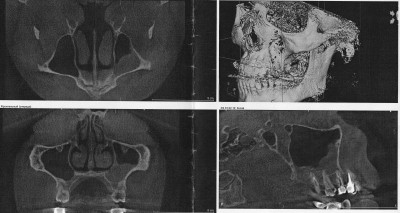

При рентгеновском обследовании в стоматологической клинике случайно обнаружили грубые подушковидные утолщения слизистой в базальных и вентральных отделах левой верхнечелюстной полости. При этом у зуба 2.4 расширена периапикальная щель, разрежение костной ткани у верхушки корня, у зуба 2.5 у верхушки корня небольшая гранулёма, над ней разрушена компактная пластина дна верхнечелюстной полости, у верхушек корней зуба 2.7 гранулёмы, компактная пластина дна верхнечелюстной полости над гранулёмами местами не прослеживается.

Можете ли подсказать, утолщение слизистой - это похоже на кисту? Можно ли тут вылечить это консервативными методами или придётся делать операцию?